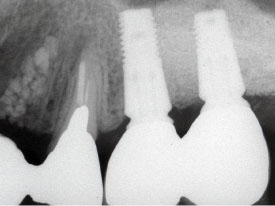

左上顎に骨を作って(上顎洞底挙上術)インプラントを入れました。

入れ歯の必要がなくなりました。

インプラントを入れることによって、自分の隣の歯を削る必要がなくなります。

Bridgeを入れるよりも良い方法です。

5年以上経過しています。

骨の吸収も全くありません。